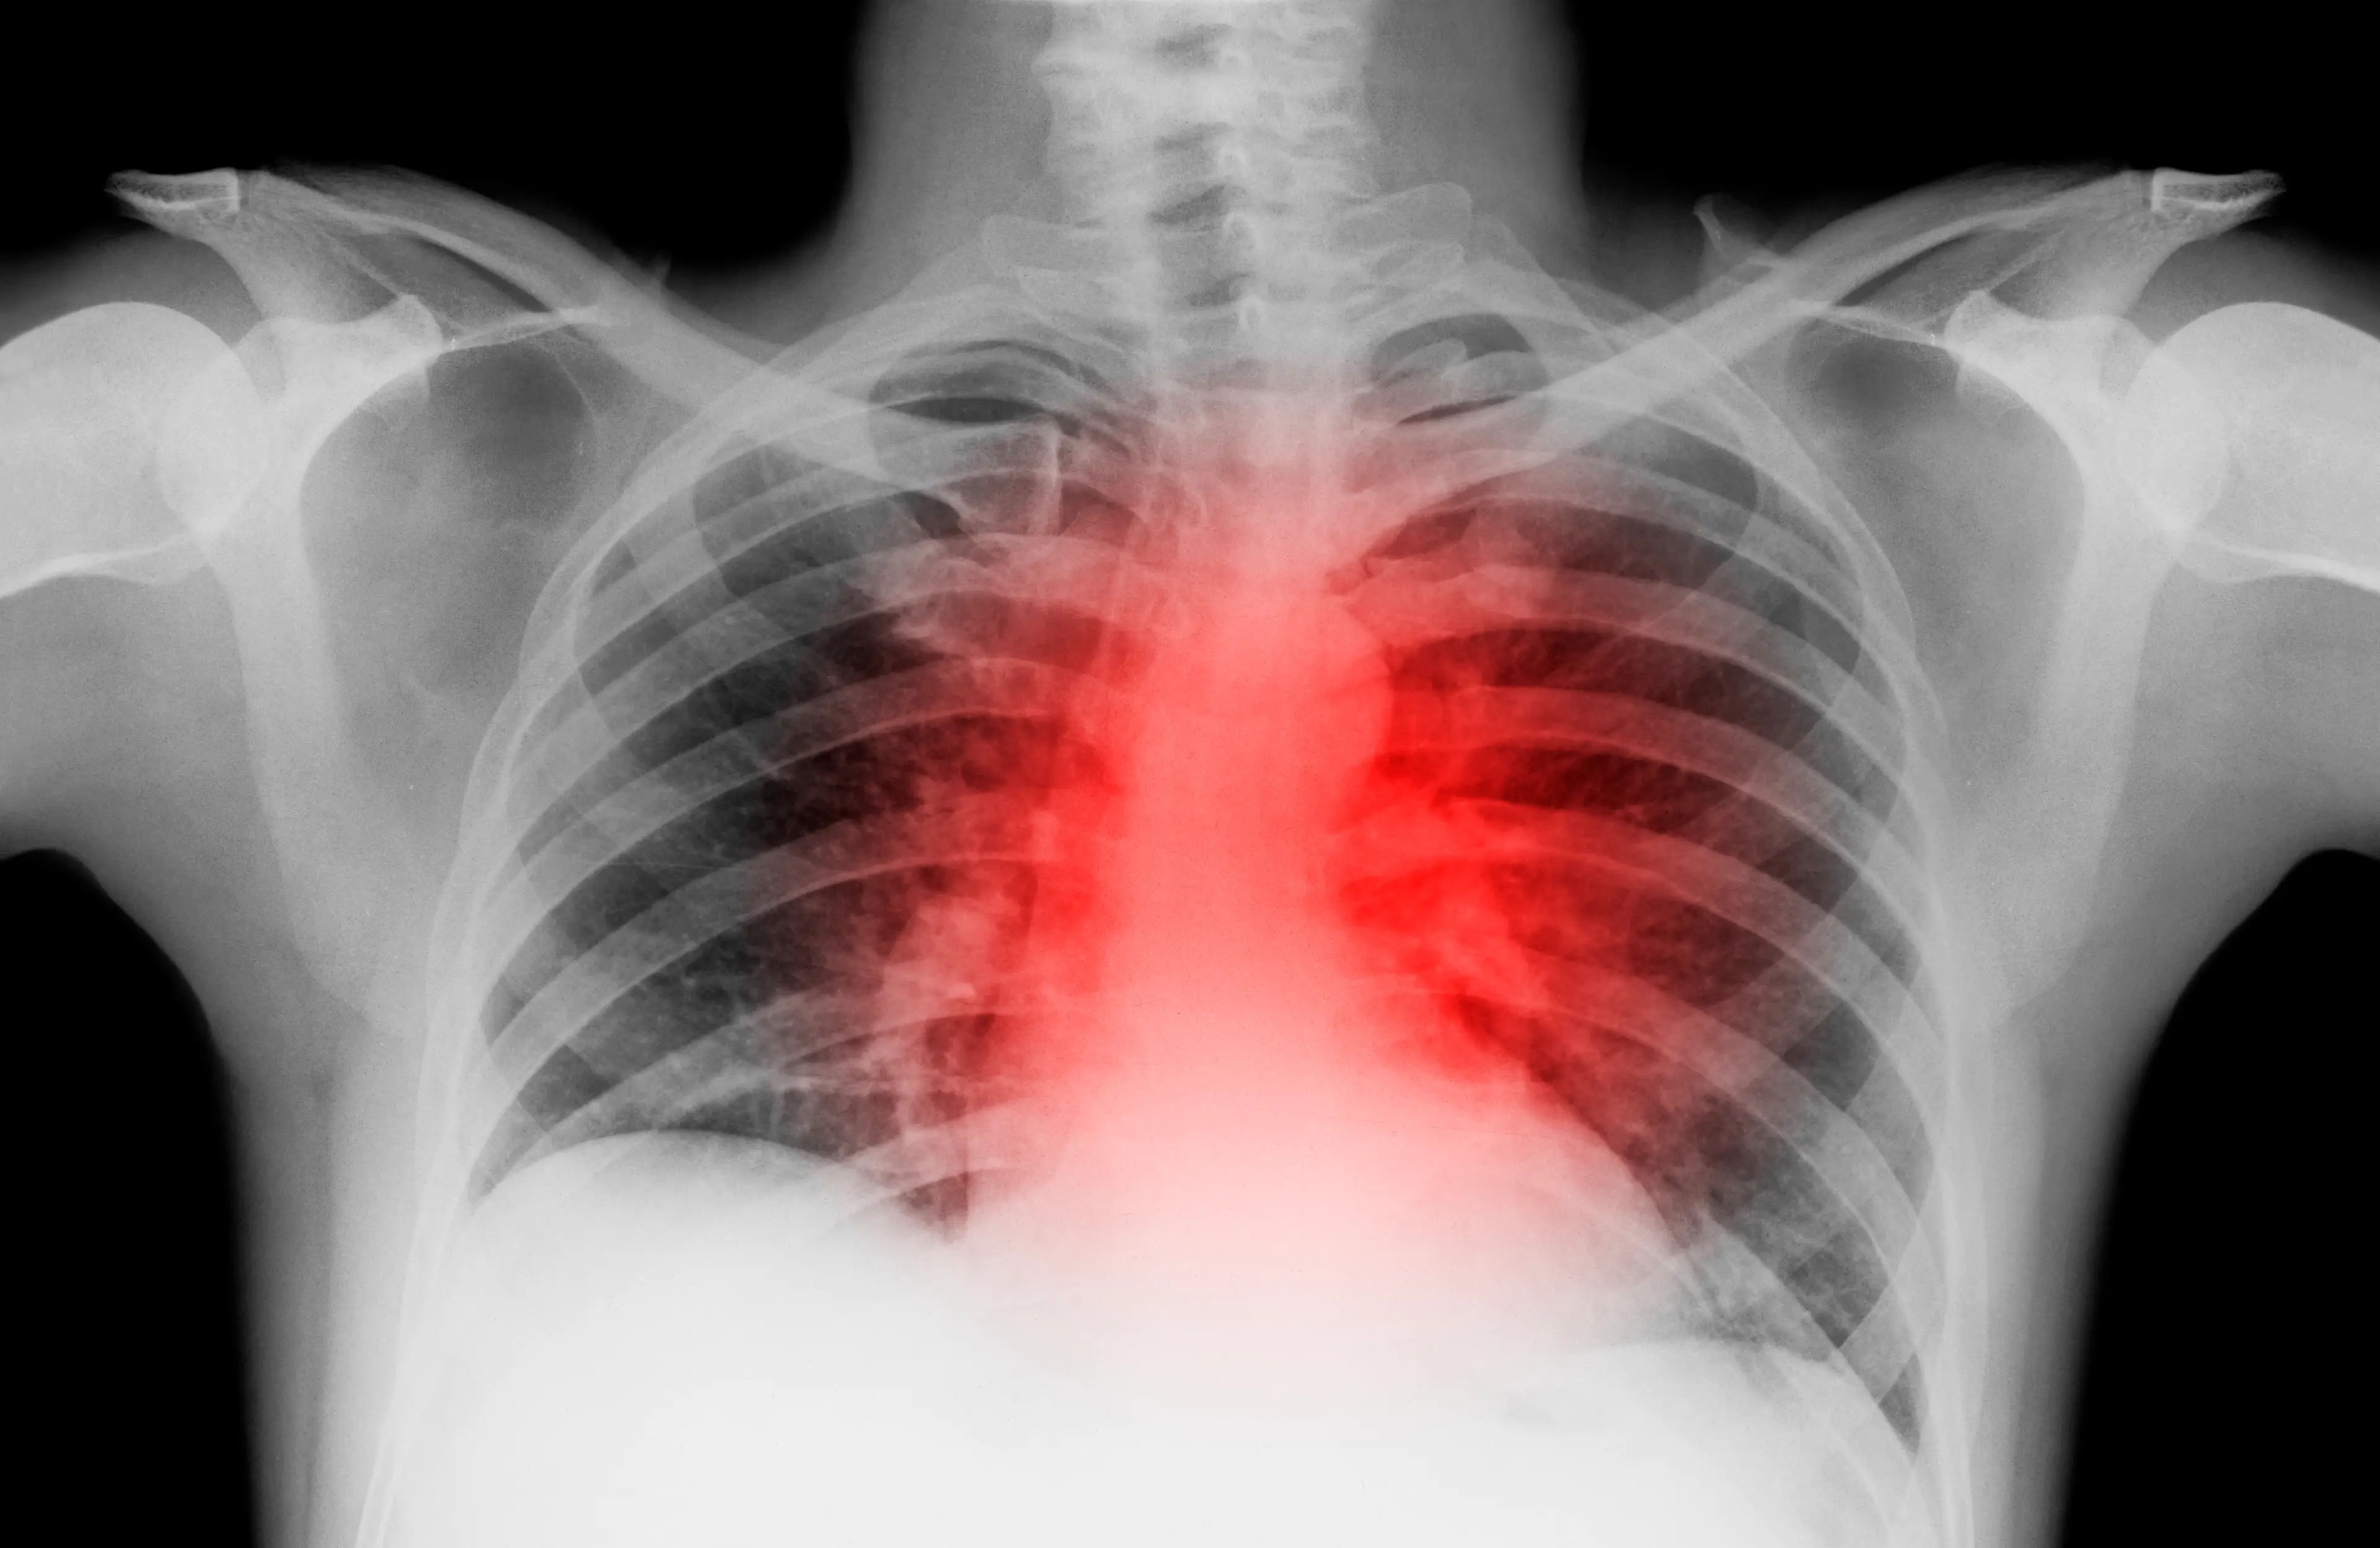

The full medical name for the condition is atrial fibrillation, and it can be caused by drinking too much alcohol.

According to the NHS website, atrial fibrillation (shortened to AFib) is where the sufferer experiences an irregular and abnormally fast heart rate.

It happens when the upper chambers of the heart don't work properly, leading them to start beating incorrectly.